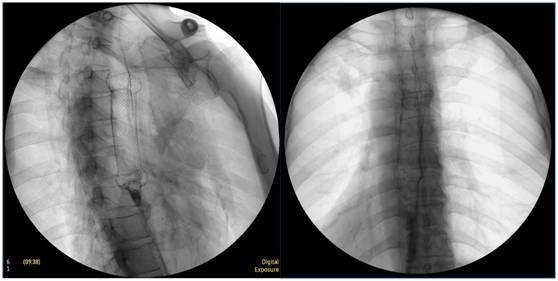

膽囊結石

ERCP膽囊顯影,見多枚結石影。